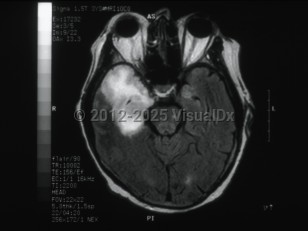

Subdural empyemaSubdural empyema